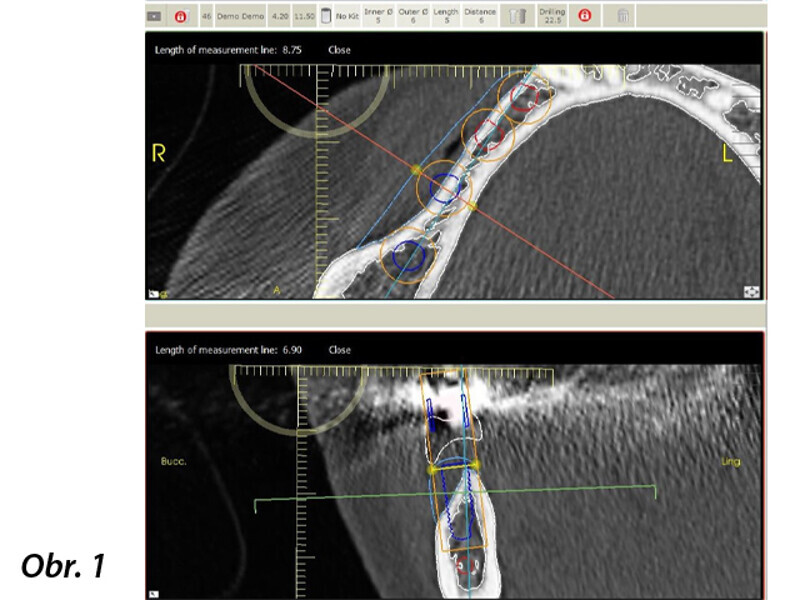

Horizontální augmentace hřebene a implantace: Dvoufázová procedura GBR